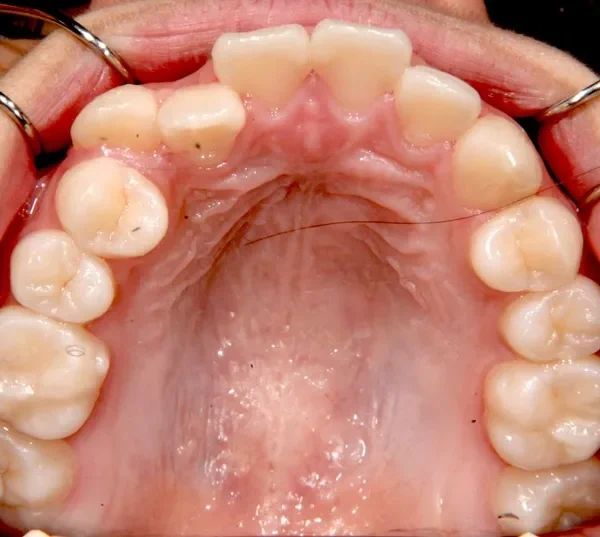

• 初診

初診